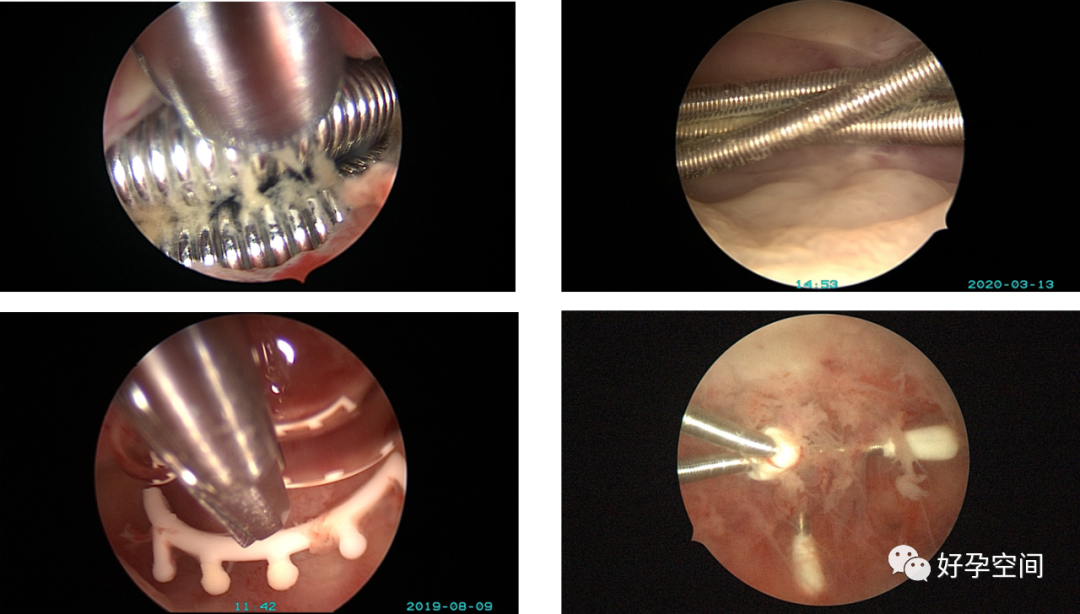

3、取环,环移位、环残留、环嵌顿、辅助安环、调整节育环位置。

4、取胚、人流及药流不全、带环受孕、切口妊娠、宫角妊娠、切口憩室、宫颈妊娠,胎盘残留、胎盘粘连、胎盘植入、子宫动静脉瘘手术。

5、阴道异物、阴道纵膈、宫腔异物、宫颈管纳氏囊肿穿刺或开窗、女性尿道检查,宫腔镜膀胱灌注、膀胱异物取出、膀胱血块清除、膀胱出血点电凝止血。

宫腔缝线异物

宫颈纳氏囊肿单极电针穿刺

宫颈纳氏囊肿开窗